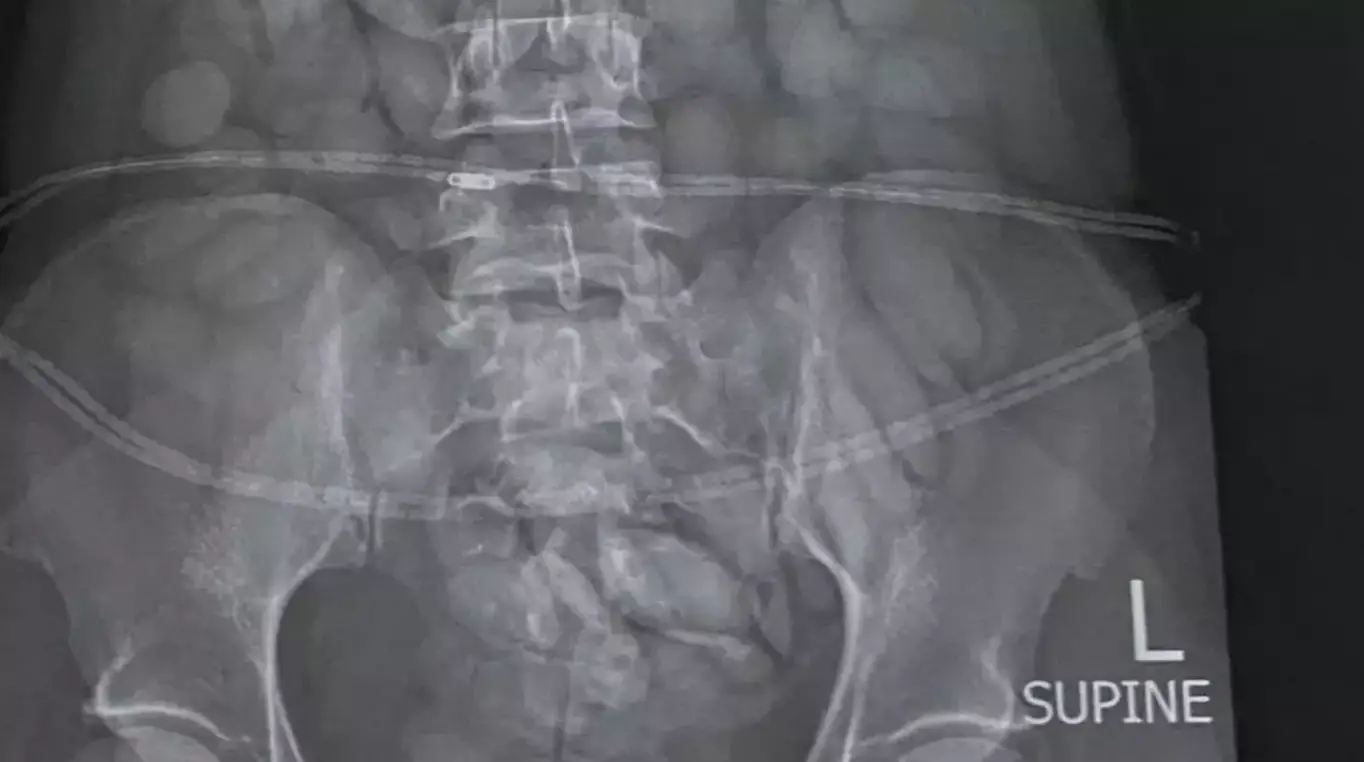

So, when the 30-year-old arrived, she was arrested and an X-ray instantly detected a number of foreign objects in her stomach.

Under police guard, she was then forced to 'release' 68 'bullets' of what is suspected to be cocaine.

Authorities say that the pellets weighed a combined total of about 850g.

Brig Athlenda Mathe, a spokesperson for the police, said: "The team immediately intercepted the drug mule as she was making her way through immigration. She was immediately arrested, taken to a local hospital where a medical X-ray confirmed and detected foreign objects in her stomach.

"The drug mule has released 68 drug bullets from her body. The estimated weight of the drugs is 850 grams. The value of the drugs cannot be determined at this stage."